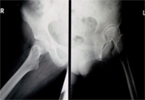

Pre

Op

33 years old female with hip pain due to avascular necrosos hips from chronic steroid ingestion

Xrays